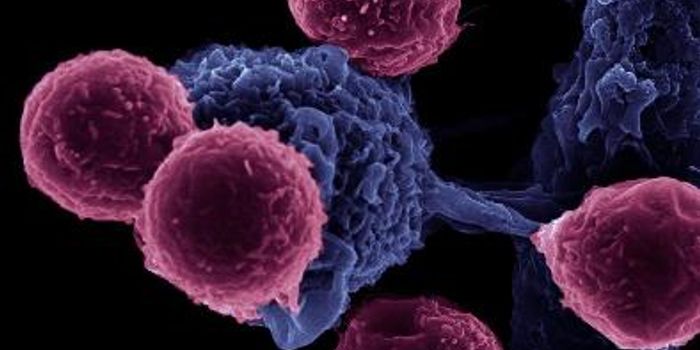

MAY 25, 2016ImmunologyHumans have specialized immune cells designed to detect and kill abnormal cells, whether they are virally-infected or ca ...

OCT 18, 2021CancerCancer immunotherapy, a treatment that directly enhances a patient’s immune system, is typically perceived as a mo ...

SEP 07, 2016CancerWhen treating cancer, doctors have turned to immunotherapy to help target actual tumors instead of attacking all rapidly ...